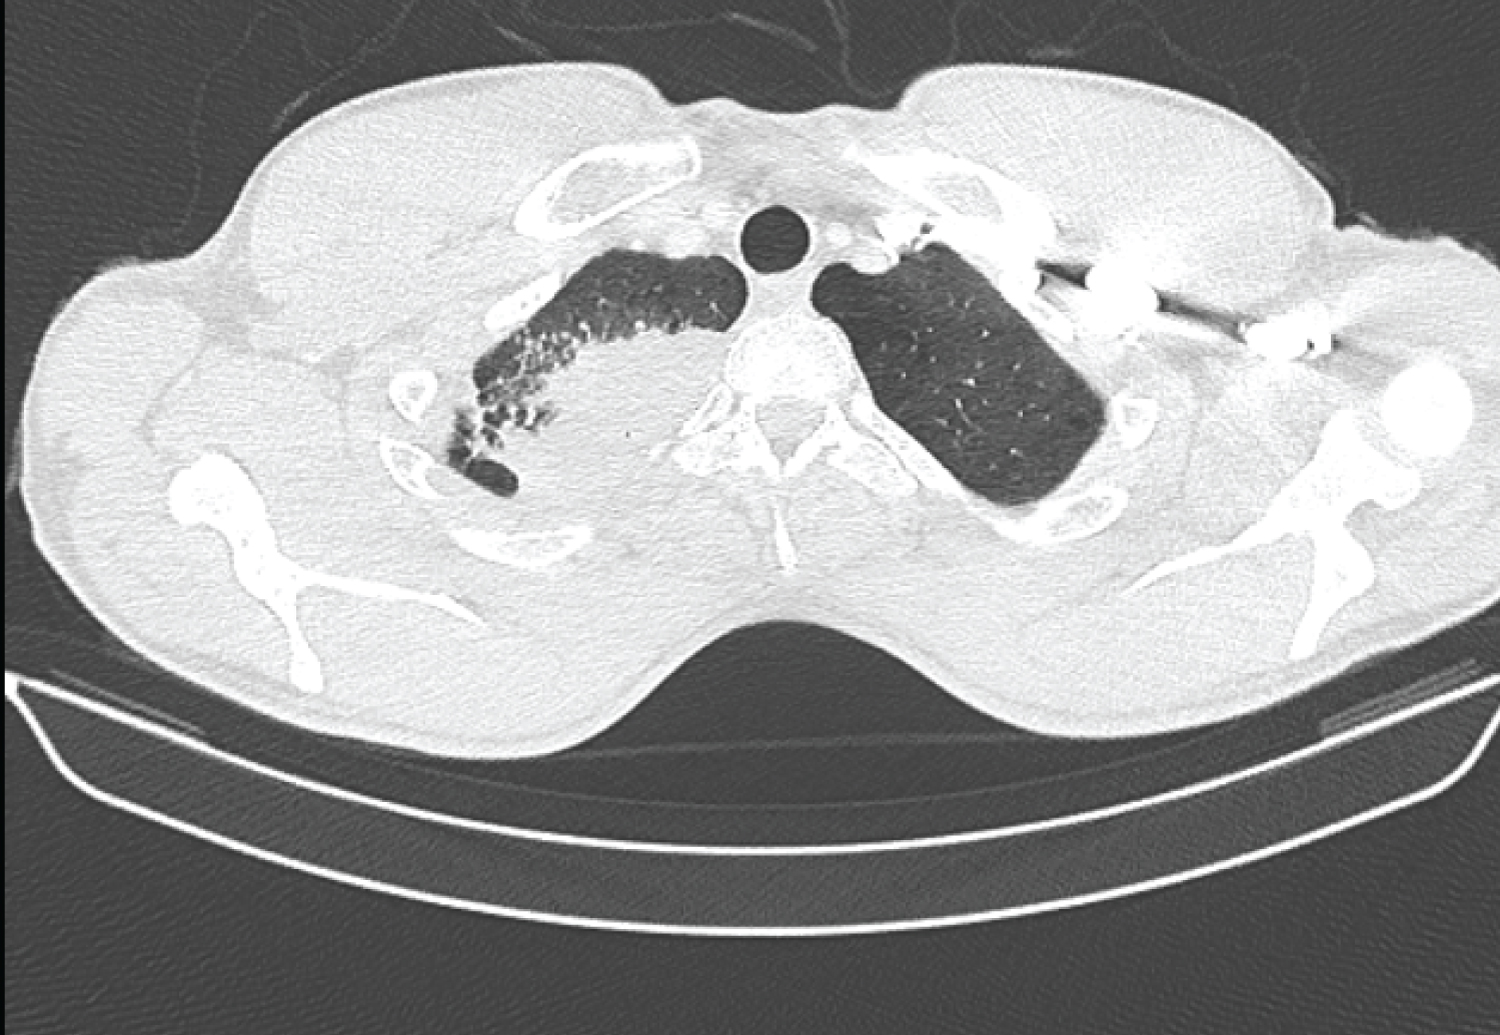

A 29-year-old man with a history of bulbar ulcer treated 2 years previously and chronic smoking at 13 packs/year was hospitalized for respiratory symptoms made up of right basithoracic pain with cough and clear sputum without fever or progressive night sweats for six months in a context of deterioration in general condition. The clinical examination was unremarkable. On the biological assessment, there was a slight inflammatory syndrome with sedimentation rate at 29 mm in the first hour and CRP at 9.8 mg/l, the blood count was normal, as were the liver and kidney assessments and the viral serologies (HBV, HCV and HIV) were negative. The search for mycobacterium tuberculosis in sputum and by gastric tube was negative on three occasions and the Quantiferon was at 2.70 IU/ml (2xN). The chest X-ray showed opacity in the apical segment of the right upper lobe. Complementary CT scan revealed significant right apical mass with alveolar condensation, pleural connections and adjacent micronodules strongly suspecting a tumor or infectious localization (Figure 1 and Figure 2). A transparietal biopsy was then performed.

Figure 3: Thoracic cross-sectional CT scan showing the right apical lung mass with alveolar condensation, pleural connections and adjacent micronodules.